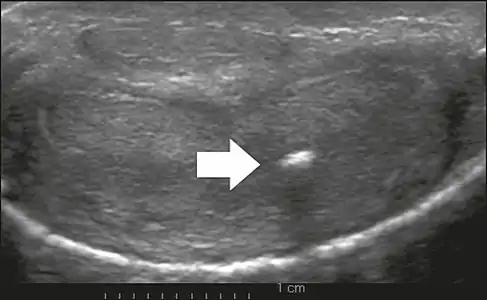

On penile ultrasonography, the typical appearance is hyperechoic focal thickening of the tunica albuginea. Due to associated calcifications, the imaging of patients with Peyronie's disease shows acoustic shadowing, as illustrated in figures below. Less common findings, attributed to earlier stages of the disease (still mild fibrosis), are hypoechoic lesions with focal thickening of the paracavernous tissues, echoic focal thickening of the tunica without posterior acoustic shadowing, retractile isoechoic lesions with posterior attenuation of the beam, and focal loss of the continuity of the tunica albuginea.

In the Doppler study, increased flow around the plaques can suggest inflammatory activity and the absence of flow can suggest disease stability. Ultrasound is useful for the identification of lesions and to determine their relationship with the neurovascular bundle. Individuals with Peyronie's disease can present with erectile dysfunction, often related to venous leakage, due to insufficient drainage at the site of the plaque. Although plaques are more common on the dorsum of the penis, they can also be seen on the ventral face, lateral face, or septum.[13]

Transverse ultrasound of the penis, in a ventral view, in the middle portion of the penis. Note the echoic image with posterior acoustic shadowing, corresponding to calcification (arrow), in the left corpus cavernosum.[13]

Transverse ultrasound of the penis, in a ventral view, in the middle portion of the penis. Note the echoic image with posterior acoustic shadowing, corresponding to calcification (arrow), in the left corpus cavernosum.[13]